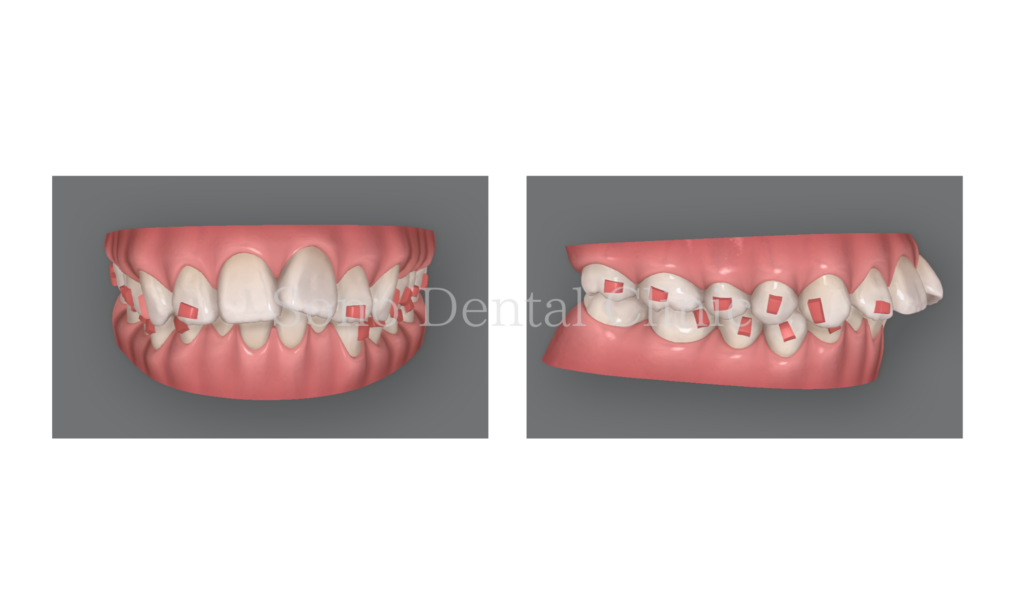

スペース不足によるガタガタ、上の前歯が出ている状態でした。

初診時:矯正治療前

はじめの治療計画ではマウスピースが47枚。

治療前:

顎の骨のスペースが足りず、歯がでこぼこしているところは歯と歯の間をほんのわずかに削り、スペース確保を行いました。